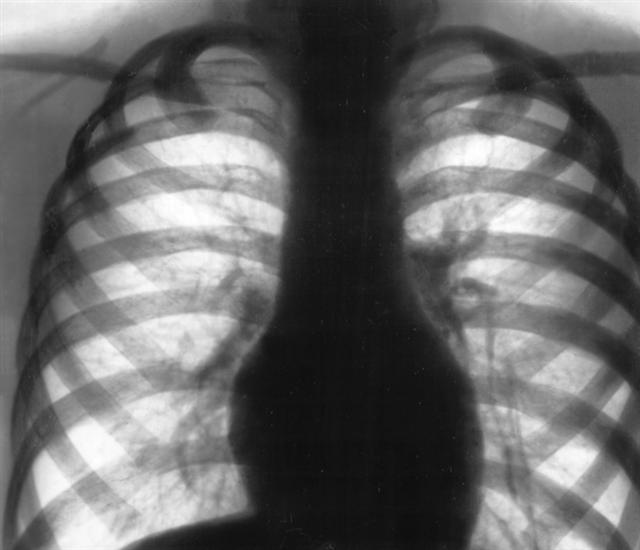

Рис. 4. Обзорная рентгенограмма грудной клетки (прямая проекция) ребенка 7 лет, больного легочной формой муковисцидоза (фаза ремиссии): эмфизема, диффузный пневмосклероз, особенно выраженный в прикорневых зонах.